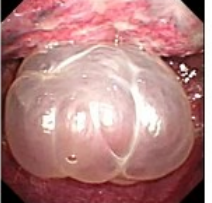

近年来,贵州航天医院各科室紧跟医学前沿,不断强技术、补短板,大力开展新技术、新项目,完成了许多高精尖、高难度、本地区“首例”的技术,填补了医院医疗技术空白,满足了群众日益增长的医疗需求。 贵州航天医院呼吸与危重症医学科是贵州省内呼吸疾病治疗规模最大,诊疗项目最全的呼吸疾病品牌科室,呼吸介入技术达到了全国先进水平,在贵州省内处于领先的地位。 本期,我们将为大家带来呼吸与危重症医学科特色技术——内科胸腔镜技术诊断和治疗胸腔疾病。 案例分享 患者苟某某,因劳累、气促,不明原因胸腔积液在某县一医院采取反复抽水等治疗手段效果不佳,当地医院考虑到患者年龄大(77岁),基础疾病较多,病情复杂,结合当地诊疗水平能力情况,建议转到上一级医院诊治,通过我院与该院建立的呼吸专科联盟绿色通道转入了我院。 患者入院后,呼吸与危重症医学科第一时间复查胸部CT,提示:右肺中叶、左肺感染,纤维化灶,左侧中量胸腔积液,右后侧胸膜轻度增厚,心包少量积液;并完善心电图、血常规、凝血功能、生化指标等术前检查。经科室专家团队集体讨论,得出患者左侧胸腔积液可能原因:结核?恶性?其他?冠心病、心功能不全、高血压病3级(高危组)、陈旧性肺结核复发?肺部感染;为进一步明确诊断,在充分评估、做好术前准备及应急预案、与患者及家属沟通的情况下,决定为患者进行内科胸腔镜检查术。 科室在患者入院第3天便实施了内科胸腔镜检查术,经检查取活检,病理不排除胸膜间皮瘤,送遵义医科大学附属医院病理会诊后诊断:胸膜间皮瘤。明确诊断后,科室专家团队为患者制定了个体化的治疗方案,患者病情很快得到有效控制,最终满意出院。半年后,医院通过电话回访,患者病情稳定,生活质量明显改善。 什么是内科胸腔镜 内科胸腔镜(medical thoracoscopy,MT)是一项微创诊断和治疗胸腔疾病的重要技术。主要应用于无创方法不能确诊的胸腔积液和胸膜疾病,通过局部麻醉后在胸壁做一个小切口,插入胸腔镜,直接观察胸膜、肺表面、纵隔等部位的病变情况,可进行活检、粘连松解及胸膜固定等操作。具有创伤小、恢复快、诊断准确性高等优点。 内科胸腔镜原理 内科胸腔镜是一项利用现代光学技术和成像技术的侵入性操作技术,应用电子支气管镜、硬质或软硬结合(半硬)的胸腔镜的一种电子内窥镜,末端装有连接着显示屏的微型摄像头。通过胸壁1-2cm左右的小切口,将内科胸腔镜及专用器械(戳卡套管)通过小切口进入胸腔,微型摄像头将胸腔内的情况投射到显示屏幕上,医生可以通过镜头全面、直观地观察患者胸腔内情况,了解胸膜病变确切位置和形态改变,还可对胸膜上的病变进行活检及治疗的操作技术,安全、微创、几乎无痛地“揭秘”不明原因的胸腔积液。 内科胸腔镜技术优势 (一)安全性高:仅需局部浸润麻醉,并发症发生率相对较低,对患者的身体条件要求较低。 (二)操作简便:操作时间短,痛苦少,患者耐受好。 (三)微创性:切口小,对患者身体损伤小,术后疼痛轻,恢复快。 (四)高分辨率成像:清晰显示胸腔内细微病变,提高诊断准确性。 (五)可直视操作:直接观察病变,进行精准活检和治疗。 (六)适用范围广:可用于不明原因胸腔积液、胸膜疾病、肺部疾病等的诊断和治疗。 (七)费用低:与外科胸腔镜比较费用低廉。 内科胸腔镜技术是贵州航天医院呼吸专科和呼吸介入诊疗优势的一部分,在2016年率先开展了内科胸腔镜技术,年手术量约100余例,已建立了快速、精准、规范、有效的一体化诊疗服务体系。目前呼吸与危重症医学科内科胸腔镜技术广泛应用于不明原因胸腔积液、气胸、脓胸的诊断和肺癌、弥漫性恶性胸膜间皮瘤等的分期,恶性或复发性胸腔积液、早期脓胸、自发性顽固性气胸的治疗。 镜下常见表现:单发或多发结节、灰白色弥漫性粟粒样结节、胸膜充血、水肿、胸膜增厚及纤维分隔或粘连带形成。 诊断方面: 胸腔积液的病因诊断。内科胸腔镜对恶性胸腔积液的诊断率可高达90%以上,胸腔镜对结核性病变诊断率极高,几乎达到96%以上。 腺 癌 恶性淋巴瘤 软骨肉瘤胸膜转移 滑膜肉瘤胸膜转移 结核性胸膜炎 治疗方面: 脓胸 肺大泡 贵州航天医院 呼吸与危重症医学科学科带头人 廖江荣 国务院政府特殊津贴专家 二级教授 主任医师 贵州航天医院副院长 国家级学术任职: 第二届中国医药教育协会介入微创专业委员会呼吸分会副主任委员 中国抗癌协会肿瘤微创治疗专业委员会常务委员 中国防痨协会结核病转化医学专业分会常务委员 第一届中国人体健康科技促进会呼吸介入专委会常务委员 中国医疗保健国际交流促进会结核病学分会第三届委员会常务委员 中国抗癌协会肿瘤微创治疗专业委员会粒子治疗学组第四届委员会委员 中华医学会结核临床专业委员会内镜介入委员 中华医学会放射学分会第十五届委员会介入学组呼吸系统介入专业委员会委员 北京健康促进会中青年专家委员会胸部疾病精准活检分委会副主任委员 中国医师协会介入医师分会第二届委员会肿瘤消融专业委员会委员 中国结核病防治综合质量控制专家指导委员会委员 亚洲冷冻治疗学会常务委员 世界内镜医师协会呼吸内镜协会常务理事 内镜临床诊疗质量评价专家委员会委员 “西部呼吸介入联盟”副理事长 专业擅长: 贵州航天医院 呼吸与危重症医学科简介 贵州航天医院呼吸与危重症医学科以呼吸危重症和介入呼吸病学为强力推手,以肺部感染性疾病及肺癌、肺小结节的早期精准诊疗、慢性呼吸疾病康复治疗为特色,以人才团队建设为核心的科室发展模式,现已成为省内呼吸疾病治疗规模最大,诊疗项目最全的呼吸疾病品牌科室。是贵州省医学重点学科、临床医学重点专科建设单位,遵义市首批呼吸重点学科、重点专科建设单位。是国家卫健委能力建设和继续教育肿瘤微创介入建设中心、贵州省县级医院微创介入培训中心、遵义市呼吸疾病临床医学中心。是国家呼吸医疗质量控制与管理哨点医院、遵义市呼吸内科专业医疗质量控制中心。是中国医药教育协会介入微创呼吸分会呼吸介入技术培训中心单位;国家卫健委海医会呼吸分会ROSE专委会“诊断性介入肺脏病学快速现场评价”培训基地;中国肺癌防治联盟“贵州航天医院肺结节诊治”分中心,中国人体健康科技促进会呼吸介入技术培训基地,贵州省中西医结合会呼吸学分会呼吸介入专委会主委单位。 基本情况 平均每年开展气管镜诊疗约4000例,经皮肺穿刺介入诊疗近千例,开展的项目包括经支气管镜(软、硬)下冷冻、氩气刀、高频电刀、球囊扩张、支架置入、超声内镜诊疗等气道介入诊疗技术,经皮肺穿刺活检及肿瘤消融术(微波、冷冻)、ROSE技术、内科胸腔镜诊疗及经血管介入诊疗技术,且多项呼吸介入诊疗技术在省内处于领先水平。 诊疗范围 航天医院呼吸专科擅长:致力于呼吸系统感染性、疑难性疾病的介入快速精准诊疗;肺癌与肺小结节早期精准诊疗水平项目提升。擅长于呼吸系统(肺)疑难病的诊断及危重病的救治,尤其在肺癌、肺小结节的早期诊断;肺癌综合靶向治疗;肺结核综合诊疗;肺部疾病的介入诊疗在省内处于前沿水平。 咨询热线 (一)呼吸与危重症医学科一病区 医生办公室:27677317 护士站:28614217 (二)呼吸与危重症医学科二病区 医生办公室:28691274 护士站:28690442 (三)呼吸与危重症医学科三病区 医生办公室:28692417 护士站:28690461 (四)呼吸与危重症医学科四病区 医生办公室:28616402、27677582 护士站:28614987、27677862